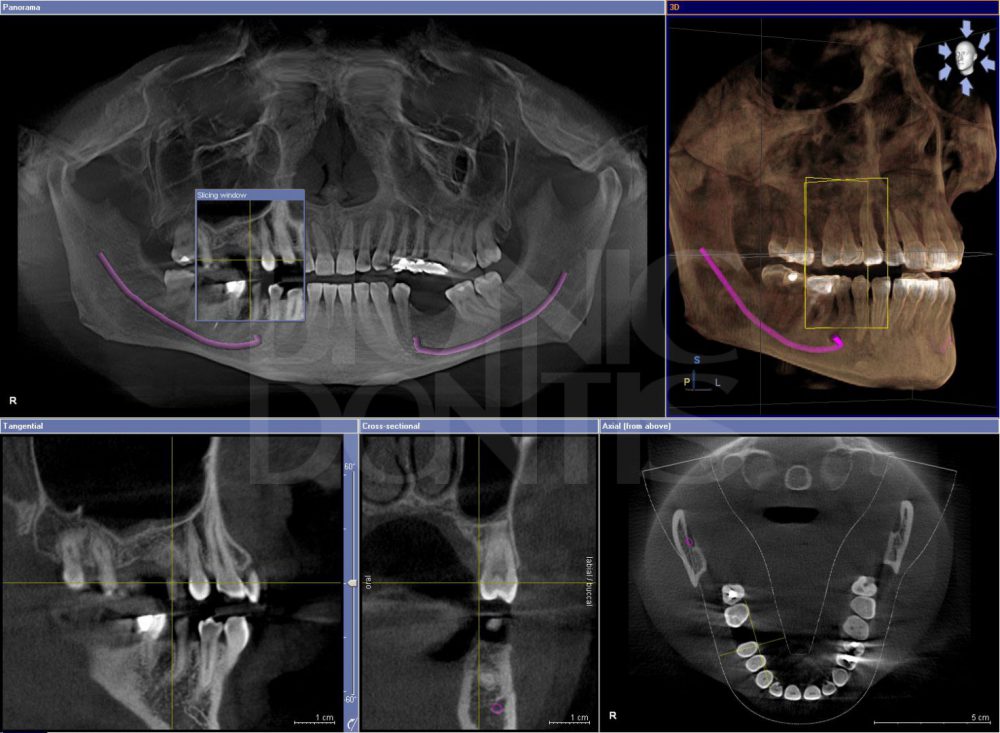

Компьютерная томография (КТ) – это мощный инструмент визуализации, который позволяет получить трехмерное изображение челюстно-лицевой области. В отличие от обычного рентгеновского снимка, КТ предоставляет гораздо больше информации, что делает ее незаменимой при диагностике сложных случаев. Мы используем КТ для:

В частности, мы использовали ИИ для автоматической сегментации зубов на КТ, что значительно упростило планирование ортодонтического лечения и установку имплантатов. Также, ИИ помог нам выявить признаки остеопороза на ранних стадиях, что позволило вовремя начать лечение и предотвратить серьезные осложнения.

Ранее, планирование имплантации занимало у нас довольно много времени. Необходимо было тщательно изучить КТ, определить положение нижнечелюстного нерва и гайморовых пазух, выбрать оптимальный размер и положение имплантата. С помощью ИИ этот процесс стал гораздо быстрее и точнее. ИИ автоматически определяет анатомические структуры, рассчитывает оптимальный угол и глубину установки имплантата, и даже моделирует результат лечения. Это не только экономит время, но и снижает риск осложнений.

Иногда кариес развивается в труднодоступных местах, например, между зубами или под старыми пломбами. Обычный рентгеновский снимок может не выявить такую проблему, а КТ с использованием ИИ позволяет обнаружить даже самые маленькие кариозные полости. Это дает нам возможность начать лечение на ранней стадии и предотвратить разрушение зуба.

Заболевания височно-нижнечелюстного сустава (ВНЧС) могут быть очень болезненными и трудно диагностируемыми. ИИ помогает нам выявлять признаки артрита, дегенеративных изменений и других патологий ВНЧС на КТ, что позволяет поставить правильный диагноз и назначить эффективное лечение.